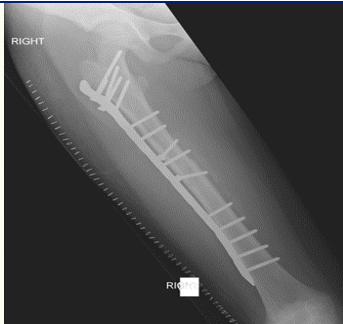

Plate and screws

What’s the name of this technique?